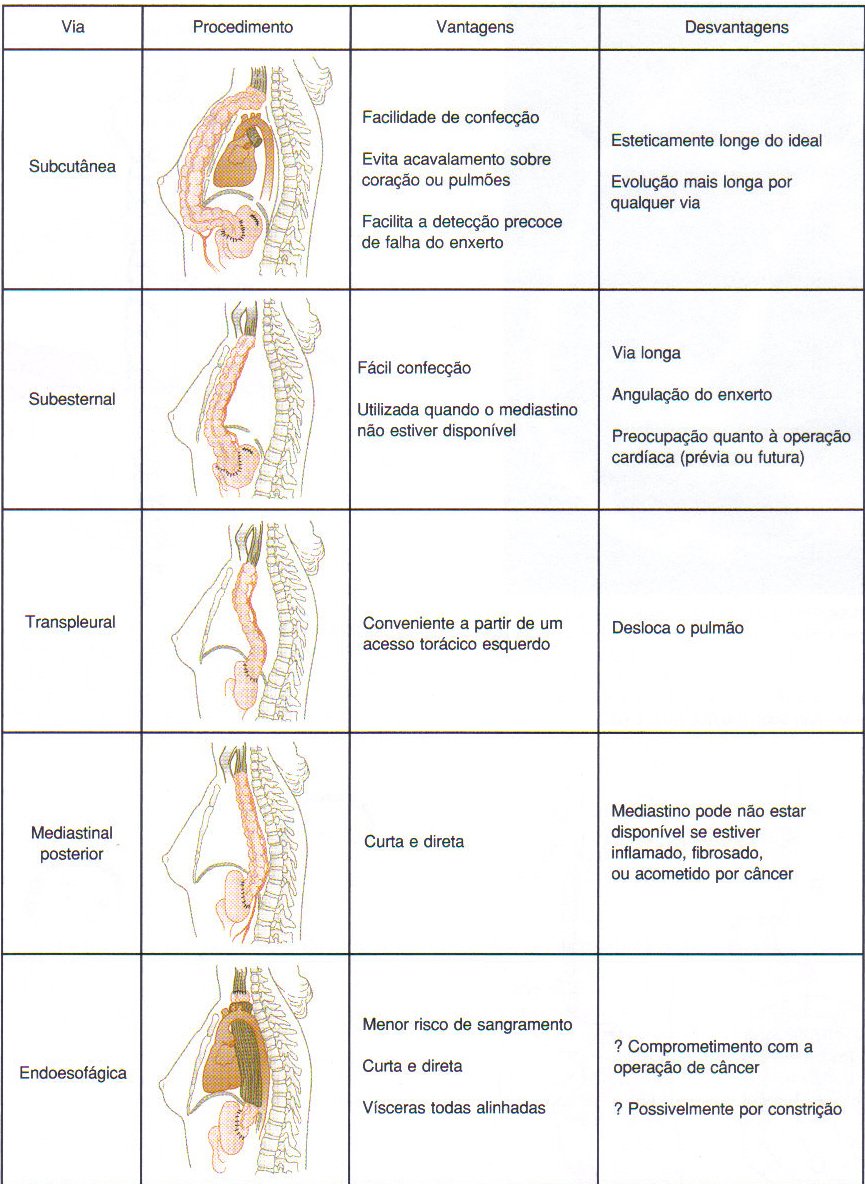

Mapa de linfonodos para câncer esofágico. A, Visão anterior. B, Visão lateral esquerda. C, Visão lateral direita. Estações ganglionares: l, supraclavicular; 2R, paratraqueal direito; 2L, paratraqueal esquerdo; 3P, mediastinal posterior; 4R, ângulo traqueobrônquico direito; 4L, traqueobrônquico esquerdo; 5, aortopulmonar; 6, mediastinal anterior; 7, subcarinal; 8M, paraesofagiano médio; 8L, paraesofagiano inferior; 9, ligamento pulmonar inferior; 10, hilar; 15, diafragmático; 16, paracardial; 17, gástrico esquerdo; 18, hepático comum; 19, esplénico; 20, celíaco A falta de serosa do esôfago tende a favorecer a extensão local do tumor.